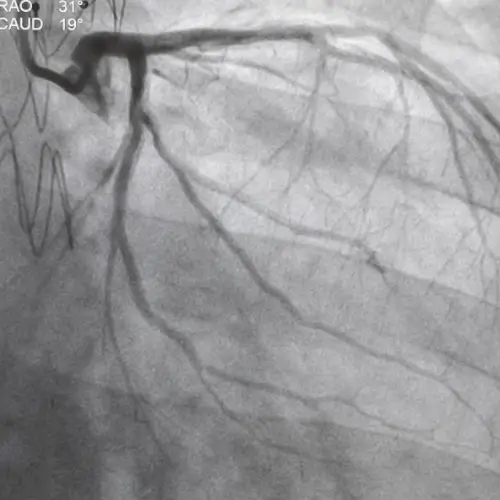

As the best Cardiology Hospital in Jalandhar, New Ruby Hospital Pvt. Ltd. is manned by senior Cardiologists trained in India and abroad. Coronary stenting is routine and performed by most of the invasive cardiologists. Patients with high-risk and multi-vessel involvement are also treated. Primary angioplasty, an approach of opening a blocked coronary artery during acute myocardial infarction, in place of thrombolysis, is practised in suitable cases.

Non-coronary interventions address a range of cardiovascular conditions. Procedures such as balloon angioplasty and stenting are performed on arteries including the subclavian, iliac, femoral, and carotid. Additionally, vascular dissections and aneurysms are treated using covered stents for effective repair.